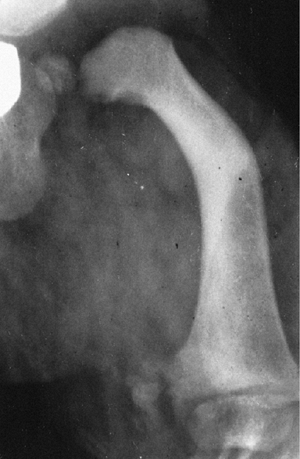

![]() |

|

Figure 29.12

In proximal focal femoral deficiency, the leg-length discrepancy is accompanied by qualitative changes, including coxa vara and bowing. |